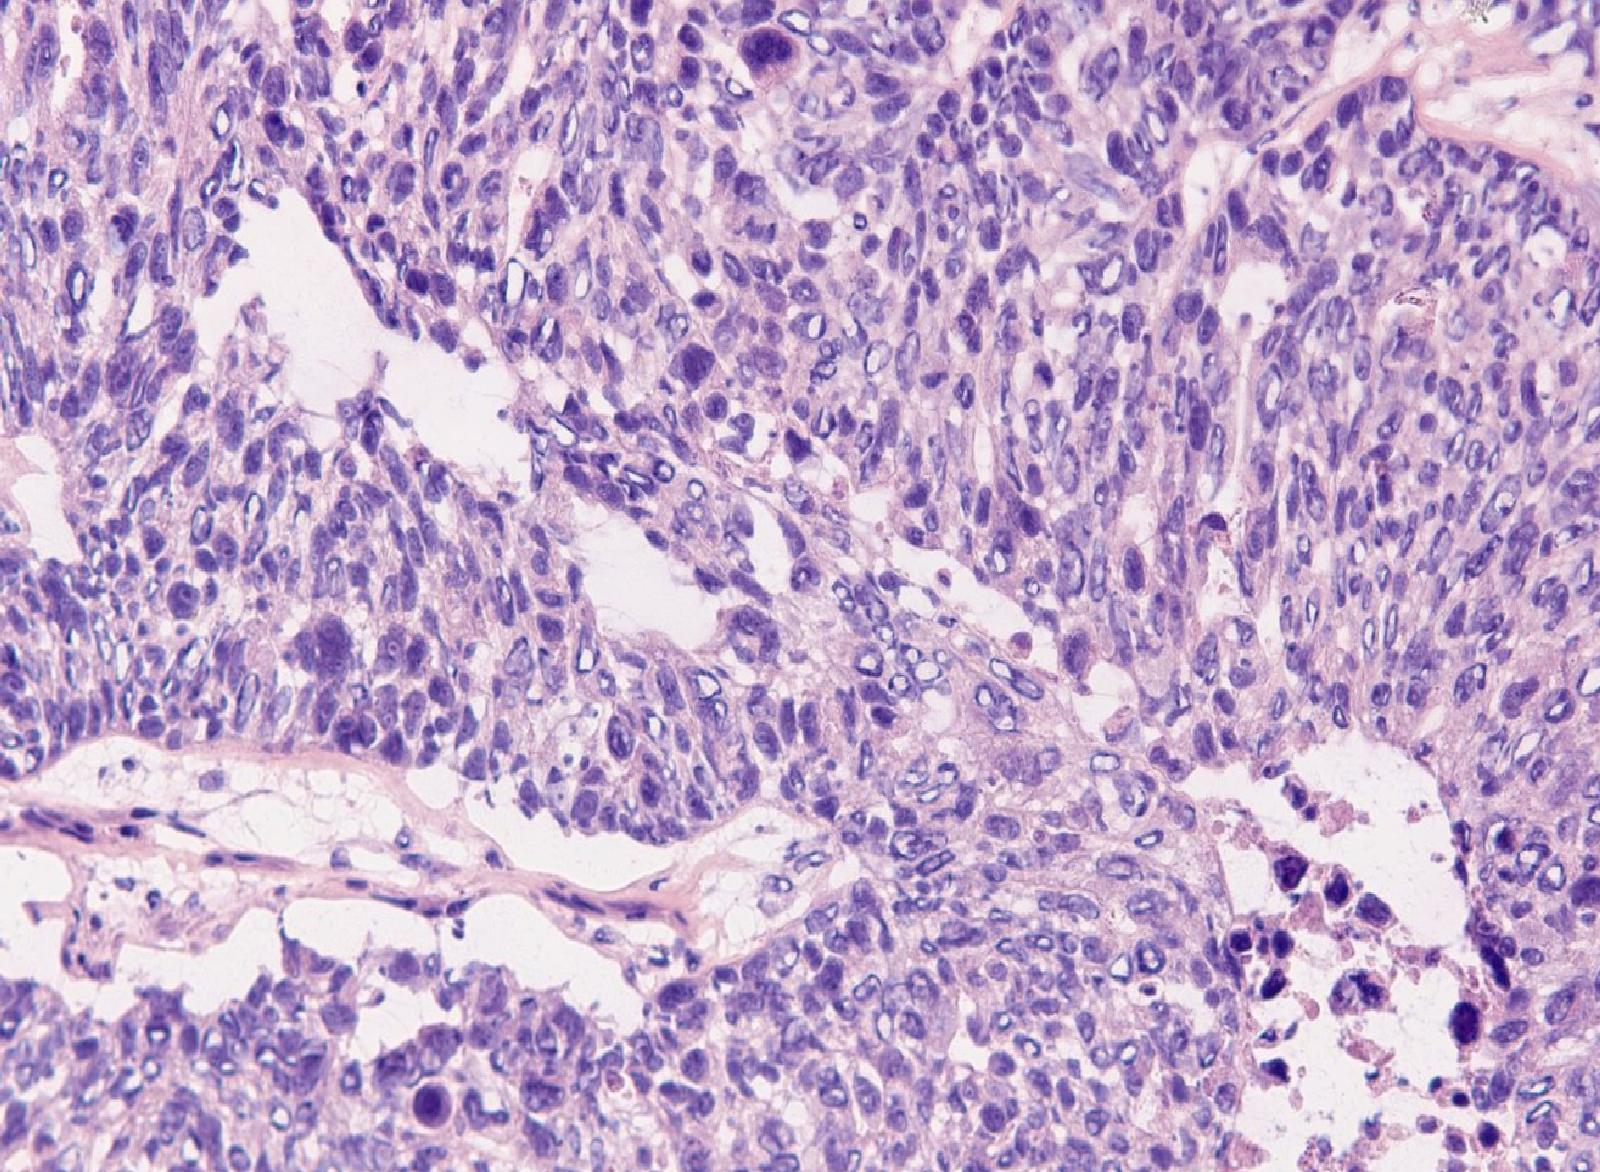

Yüksek dereceli yumurtalık over kanseri (HGSOC), kadınlar arasında en ölümcül kanser türlerinden biri olarak öne çıkmaktadır. Bu kanser türünün düşük sağkalım oranları, erken teşhis için gerekli biyomarkerlerin eksikliği ve sınırlı tedavi seçenekleri, HGSOC’nin tedavisini son derece zor hale getirmektedir. Mevcut tedavi yöntemleri arasında, en yaygın olarak kullanılan kemoterapi ajanı cisplatin yer almakta, ancak bu tedaviye direnç gelişimi sıkça gözlemlenmektedir.

Son zamanlarda araştırmacılar, forskolin adlı bir bileşiğin, hücresel bir sinyal yolu olan siklik AMP’yi aktive ederek kanser hücrelerinin çoğalmasını baskıladığını keşfetmişlerdir. Ancak, forskolin’in klinik kullanımı sınırlıdır. Knarr ve meslektaşları, forskolin’in bir türevi olan colforsin daropate‘in HGSOC hücrelerinde özellikle hücre ölümüne yol açtığını, buna karşın normal fallop tüpü ve over hücrelerine zarar vermediğini belirlemişlerdir. Colforsin daropate, MYC sinyalini zayıflatarak HGSOC’nin invazyonunu engellemektedir.